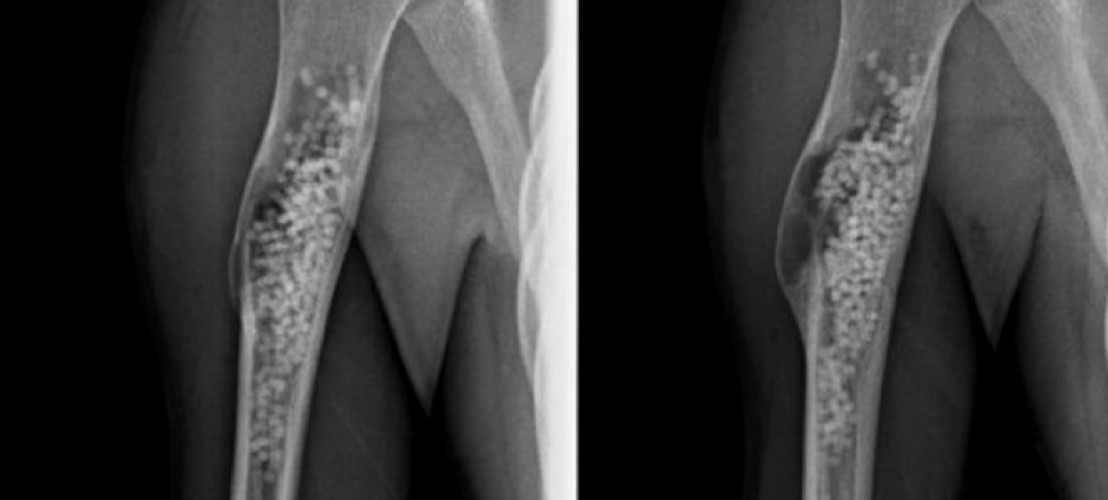

La risposta sembra essere stata data da John Dormans del Children’s Hospital di Philadelphia che per primo ha pubblicato una casistica di pazienti trattati con perle di solfato di calcio OsteosetTM, Wright Medical Technology, Arlington, TN) introdotte a riempire la cavità ossea previo curettage della pareti della cisti e con apertura del canale midollare sul Journal Paediatric Orthopaedics nel 2005. Questo ha notevolmente migliorato l’ approccio che risulta essere mini invasivo attraverso un’ incisione di un paio di centimetri che consente di giungere sulla corticale dell’ osso. Dopo avere avere pulito le pareti della cisti con una curette e creato comunicazione tra la cisti e il canale midollare grazie al suo introduttore si inseriscono le perle di solfato di calcio procedendo a riempire la cavità cistica e procedendo man mano con la curette a compattare e stipare le pellets in modo tale da ben riempire la cisti. In tale fase risulta essere molto importante il controllo in scopia dello stato di riempimento della lesione in modo tale da consentire di non lasciare zone libere all’ interno della cisti. Quando la cisti risulta essere ben riempita sarà sufficiente suturare la piccola incisione e mantenere a riposo l’ arto senza dover procedere a immobilizzazioni gessate. Per quanto riguarda l’arto superiore sarà più che sufficiente consigliare di mantenere il braccio al collo per qualche giorno nel periodo post operatorio.

Una radiografia viene eseguita il giorno successivo all’ intervento, un’ altra a distanza di 1 mese, quindi a 3, 6, 12 mesi dall ‘intervento.

La capacità assolutamente osteoinduttiva delle perle di solfato di calcio che risultano ben presenti alla radiografia post operatoria, dando un aspetto “impallinato” della lesione, dopo un mese sono pressocchè quasi totalmente scomparse, sostituite da neoapposizione ossea.

I controlli a 3, 6, 12 mesi servono a verificare che non vi sia una riaccensione del processo litico che, secondo la letteratura, è evento suscettibile nel circa il 20% dei casi. In tal caso potrà essere ripetuta l’ intera procedura sopra descritta. La cisti solitaria nella maggior parte dei casi tende a guarire con neo apposizione ossea grazie all’ osteoconduttività indotta dalle pellets di solfato calcico che, scomparendo nell’ arco di un mese, non risulta ostacolare la perfetta visualizzazione della regione litica come nei casi in cui vengano introdotti materiali a base di trisolfato calcico che permane a lungo con area di radio opacità che impediscono di valutare se il processo patologico sia attivo o sia in fase di risoluzione.